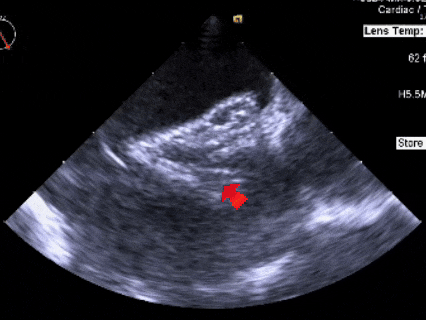

锁定后评估

彩色多普勒血流成像显示无残余分流存在

释放后多切面下观察

封堵器位置正确、形态良好